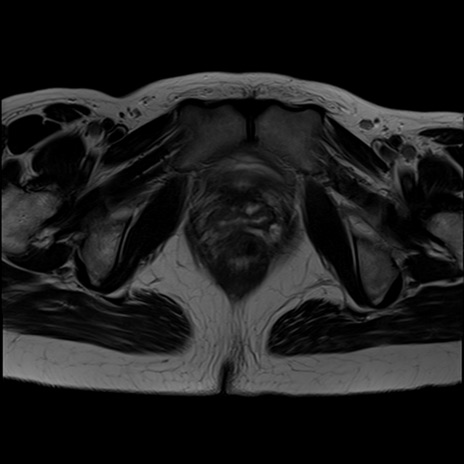

症例39 T2WI(横断像)

MRI(4日後)